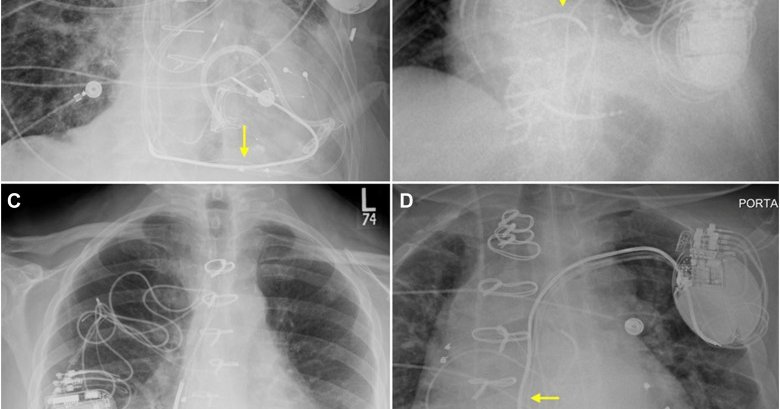

Epicardial Placement of Implantable Cardioverter-Defibrillators in Adults: Technical Considerations, System Performance, and Clinical Outcomes #OpenAccess

@PoojitaShivamu1 @PennCardiology

Surgical implantation of epicardial implantable cardioverter-defibrillator (ICD) is considered when transvenous ICD placement is not feasible because of congenital anomalies, venous obstruction, or...